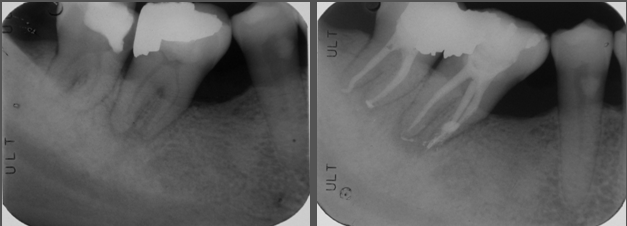

根管治療後陶瓷冠塊體-二次蛀牙-#37

根管治療

非手術根管治療